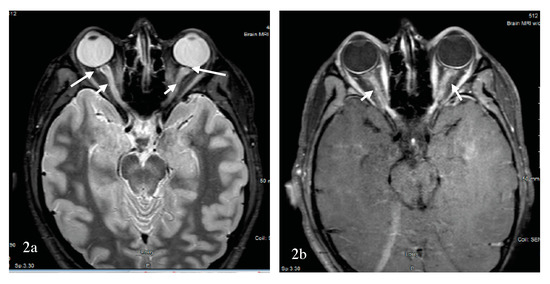

4. Optic Neuritis: From Clinically Isolated Syndrome to MS, NMOSD and Others

4.3. Neuromyelitis Optica Spectrum Disorder-Associated Optic Neuritis